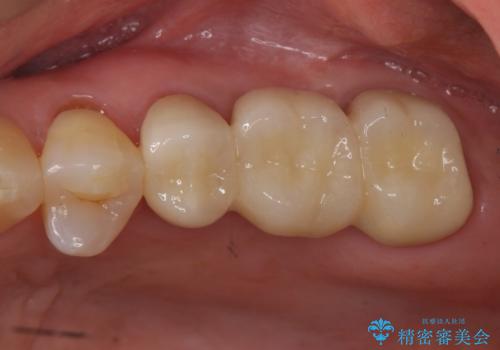

奥歯も少なく、左上奥歯はブリッジにすることになりました。

- 140.8万円(矯正治療:104.5万円、奥歯ブリッジ:36.3万円[ジルコニアクラウン10万円x3 仮歯x1万円x3])費用は治療当時の料金となります